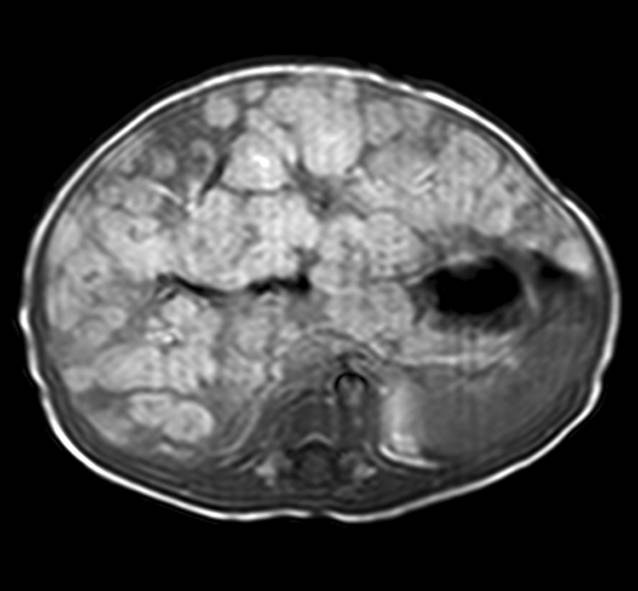

Abb. 5

Patientin 2. Das Magnetresonanztomogramm im Alter von 6 Monaten zeigt eine deutliche Größenreduktion der Läsion

Bei dieser Patientin wurde bereits in einem pränatalen MRT eine ausgedehnte, überwiegend makrozystische Veränderung mit Punctum maximum inframandibulär beidseits, die bis an den Meatus acusticus externus, die Schädelbasis und die Infratemporalregion heranreichte, beschrieben (Tab. 1). Es fanden sich Ausläufer bis in den Zungengrund sowie den Oro- und Hypopharynx. Ab dem 2. Lebenstag erhielt die Patientin Sirolimus. Die erste postpartale MRT erfolgte am 5. Lebenstag und zeigte eine gemischte groß- und kleinzystische lymphatische Malformation (Abb. 4). Zur Sicherung der Atemwege erfolgt unmittelbar postpartal die gesetzte Intubation und am 16. Lebenstag die Anlage eines Tracheostomas sowie die erstmalige Sklerosierung der großzystischen Areale durch Instillation von OK 432. Die Betreuung erfolgte interdisziplinär durch Kinderchirurgie, pädiatrische Hämato-/onkologie und pädiatrische Pulmonologie. Weitere OK-432-Instillationen wurden im 2. und 5. Lebensmonat durchgeführt. Sirolimus wurde insgesamt ausgezeichnet toleriert. Die Dosen wurden nach Körpergewicht und Serumspiegel entsprechend adaptiert und lagen zwischen 0,035 und 0,0625 mg/kg und Tag. Es traten zwar mehrfach fieberhafte respiratorische Infekte auf, die jedoch nicht über das bei nicht immunsupprimierten Patienten in diesem Alter übliche Ausmaß hinausgingen. Es kam klinisch und radiologisch zu einer deutlichen Größenabnahme der lymphatischen Malformation, die auch in der im Alter von 6 Monaten durchgeführten MRT bestätigt wurde (Abb. 5).